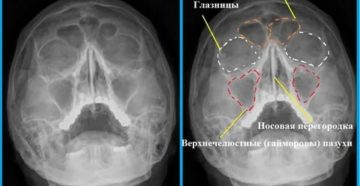

Рентген пазух носа: что показывает, как часто можно делать, расшифровка При длительных заболеваниях органов дыхания,…